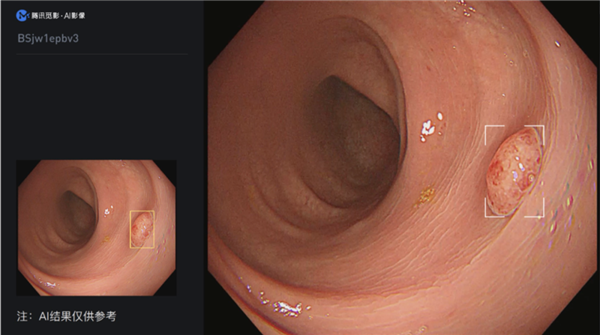

“结肠息肉电子内窥镜图像辅助检测软件”需配合结肠镜检查,从电子内窥镜图像处理器输出的视频流中导入视频图像信号,经过深度学习算法分析后将疑似息肉位置在视频中进行实时标记,提醒医生关注疑似病灶。

人工智能为临床医生提供实时的辅助提醒